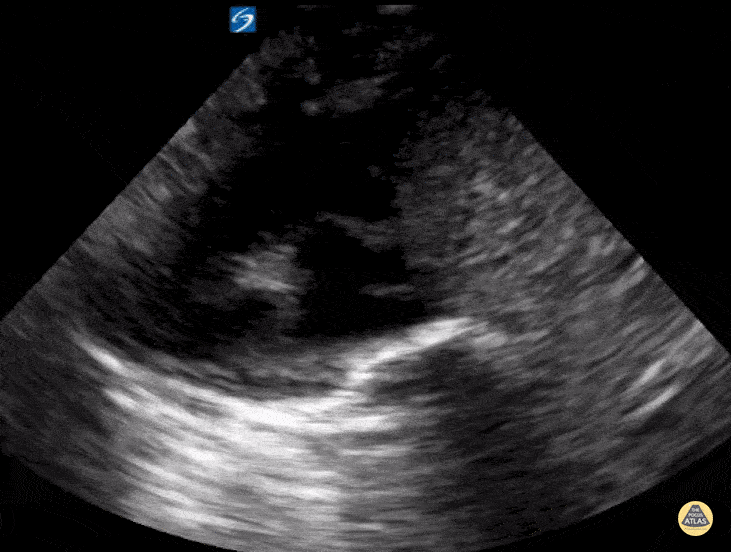

4 month old with pulmonic stenosis with tachycardia. IVC fluid tolerant. Contributor: Kathryn Pade, MD